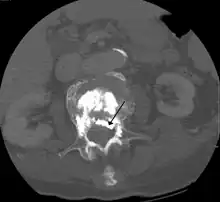

During the procedure, bone cement is injected with a biopsy needle into the collapsed or fractured vertebra. The needle is placed with fluoroscopic x-ray guidance. The cement (most commonly poly methyl methacrylate (PMMA), although more modern cements are used as well) quickly hardens and forms a support structure within the vertebra that provide stabilization and strength. The needle makes a small puncture in the patient's skin that is easily covered with a small bandage after the procedure.[2]

Some of the associated risks are from the leak of acrylic cement to outside of the vertebral body. Although severe complications are extremely rare, infection, bleeding, numbness, tingling, headache, and paralysis may ensue because of misplacement of the needle or cement. This particular risk is decreased by the use of X-ray or other radiological imaging to ensure proper placement of the cement.[2] In those who have fractures due to cancer, the risk of serious adverse events appears to be greater at 2%.[23]

The risk of new fractures following these procedures does not appear to be changed; however, evidence is limited,[17] and an increase risk as of 2012 is not ruled out.[25] Pulmonary cement embolism is reported to occur in approximately 2-26% of procedures.[26] It may occur with or without symptoms.[26] Typically, if there are no symptoms, there are no long term issues.[26] Symptoms do occur in about 1 in 2000 procedures.[22] Other adverse effects include spinal cord injury in 0.6 per 1000.[22]